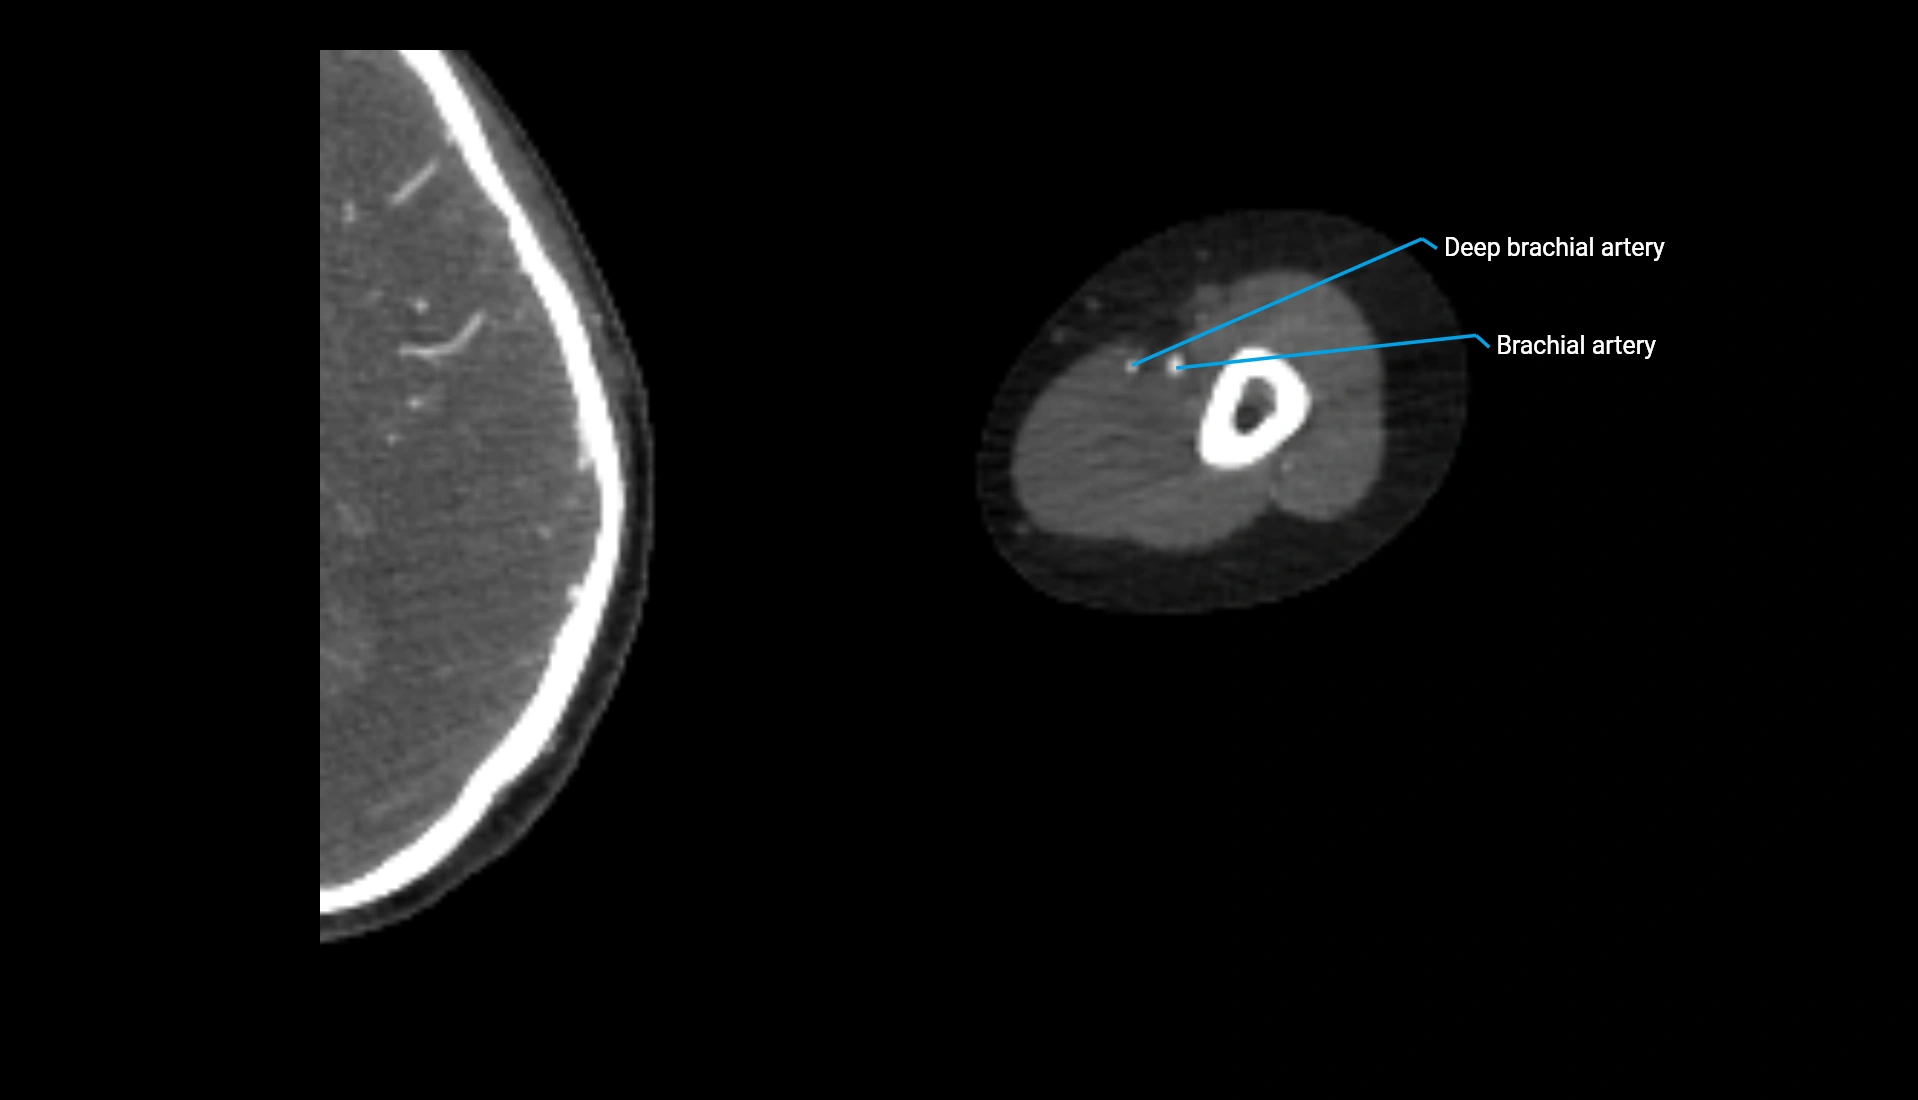

CT Appearance

Non-Contrast CT:

• Cortex: High-density, sharply defined

• Subchondral bone: Dense cancellous matrix

• Articular surface: Smooth concave contour articulating with the capitellum

• Excellent for evaluating bone integrity, alignment, and subtle fractures